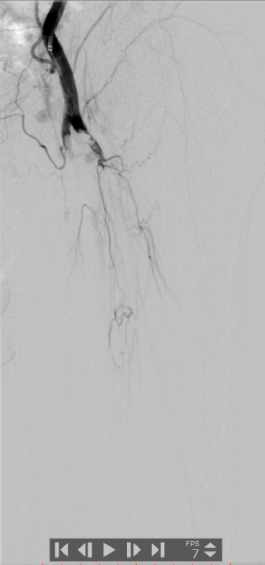

术前下肢动脉CTA提示:左下肢股、腘动脉长段闭塞,膝下动脉主干未见显影,可见少量侧支血流。

血管外科姜坤主任团队仔细分析患者病情,该患者在动脉硬化闭塞基础上继发血栓形成,且血栓负荷量大,身体状况差,行麻醉及开放手术取栓的风险大,遂制定了微创腔内的手术方案,采用动脉机械血栓清除+血管成形术。

术中选用Rotarex导管行血栓清除,对管腔内残留的血栓放置溶栓导管,最后采用球囊扩张狭窄病变,管腔获得满意。